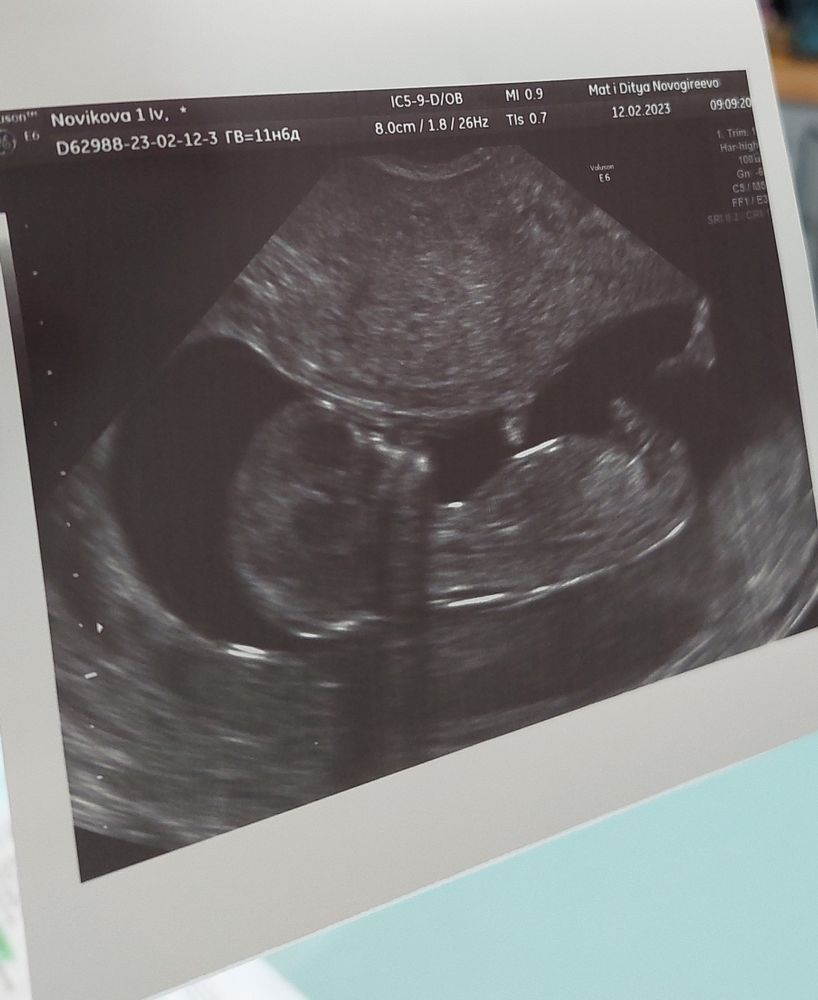

1й скрининг УЗИ пройдено 🫣

По УЗИ все, что можно диагностировать на этом сроке, в норме.

Малышка вела себя очень спокойно, доктор похвалила, что очень удобно все замерять.

Так интересно, я, наверное, себе придумала, но она такая прям девочка, изящная....ручки сложила, ножкой потихонечку помахивает😊